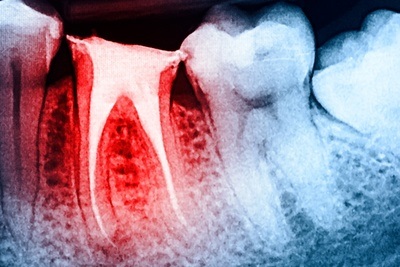

Carie dentaria

La carie dentaria è un procedimento patologico che interessa solo i tessuti duri del dente, nonostante anche la polpa partecipi alla lesione quando viene raggiunta dai microrganismi o dagli enzimi batterici.

Questi ultimi, infatti, stimolano un processo infiammatorio della polpa, giungendo a contatto con essa, veicolati dal buco creato dalla carie.

La pulpite rappresenta una complicanza molto comune delle carie, soprattutto nel dente deciduo, caratterizzato da un volume pulpare molto esteso e da una ridotta componente dentinale. |